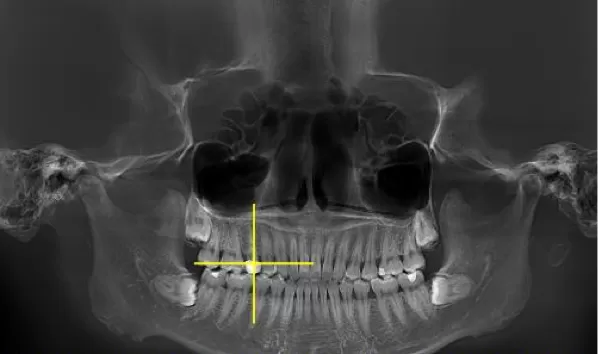

X-rays before treatment

[Panoramic Radiography/Lateral Cephalogram]